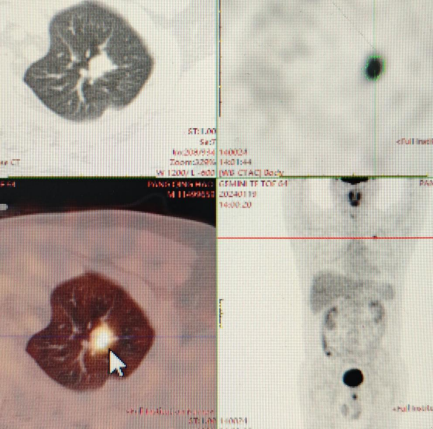

通过智能影像筛查、实体/液体活检技术、内镜精查活检、遗传风险评估、动态监测等多种先进技术发现癌前病变或早期肿瘤,实现早诊早治、防治结合。